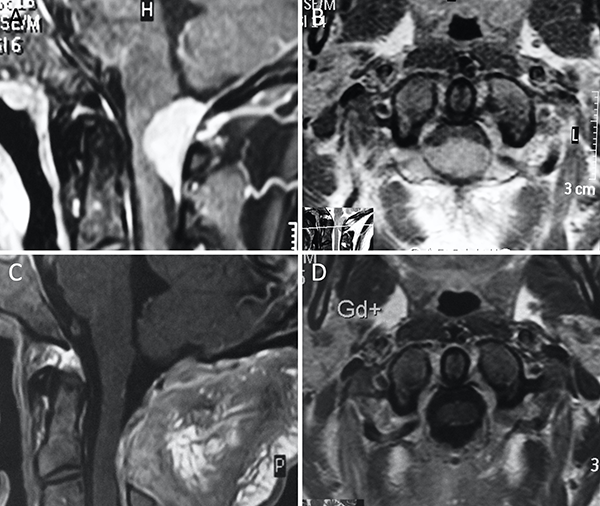

Figura 9. Meningioma del foramen magno anterior. A-B: RM preoperatoria; C-D: RM postoperatoria.